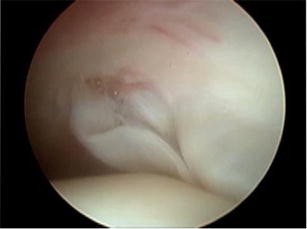

Fig. 1

Fig. 2

Fig. 3

Fig. 4

Fig. 5

Fig. 6